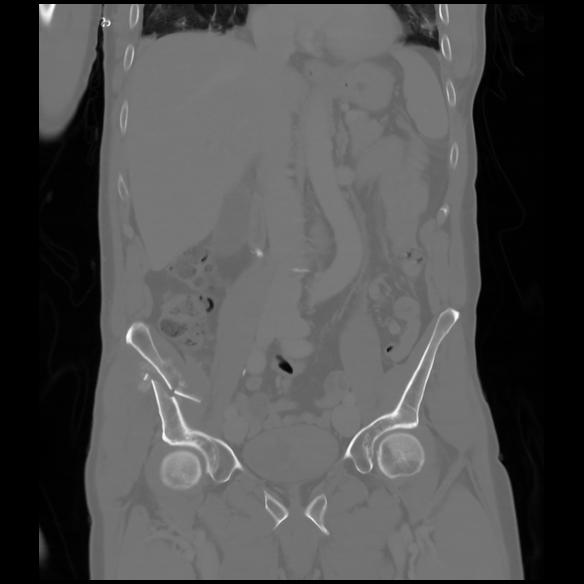

6 CUERPO,CE,Coronal,3.000,CUERPO,Coronal,